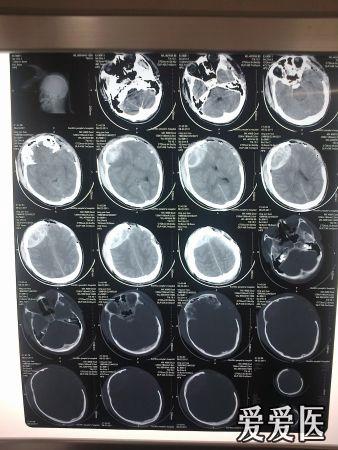

弥漫性脑挫裂伤治疗求助

图片尺寸2656x3984